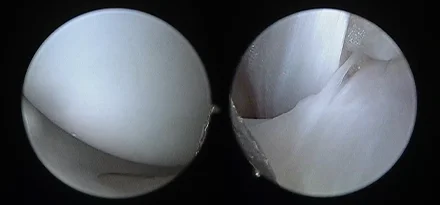

관절경

개,고양이 들은 다양한 관절질환이 존재하고, 복합적으로 존재하는 경우도 빈번합니다.

정확한 진단이 나지 않은 뒤 수술을 하게되면 증상개선이 더디거나 개선이 안될 수 있어, 정확한 진단이 필요합니다.

관절의 경우 X-ray 촬영등으로 진단의 한계가 명확하며, 상위 검사인 CT, MRI 촬영으로도 진단의 한계가 있습니다.

이때 관절경은 내부 구조물들을 직접 시각화 하여 보다 정확한 관절의 상태를 확인하고 진단할 수 있으며, 진단과 치료를 동시에 진행하는 경우도 있습니다. 대표적으로 십자인대단열(CCLR), 골연골염(OCD), 자뼈꿈치돌치유합부전(UAP), 내측관상돌기질환(MCD) 등에 활용될 수있습니다.

관절경 팔꿈치관절(Elbow) 확인

관절경 무릎관절(Stifle) 확인 (반월판 및 십자인대)

* 리본동물의료센터 케이스 사진으로 무단 복제 및 도용을 금지합니다.